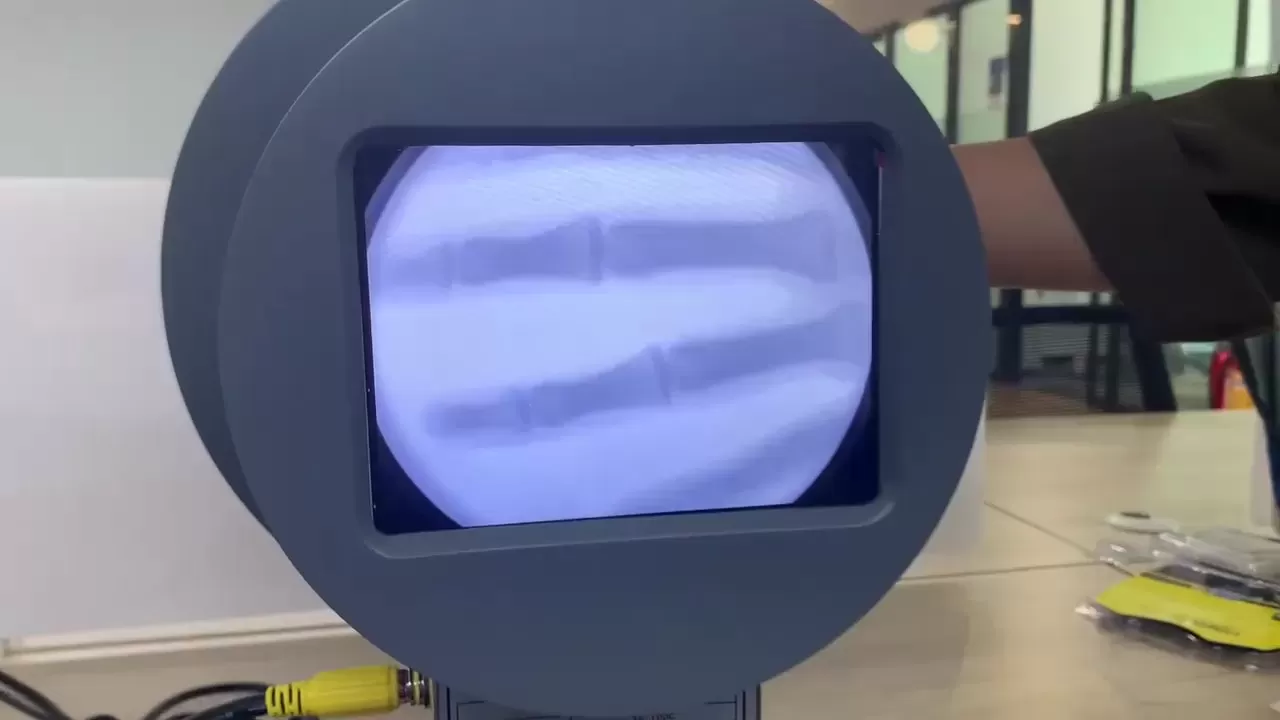

1: No darkroom, real-time imaging, display synchronization display, can be connected to the computer storage printing;

2: High gain, high sensitivity, high spatial resolution, short response time;

3: Simple design, small size, light weight, can be used by hand;

4: Low radiation dose, safe and reliable, easy to operate.

| Product Name | Portable X-Ray Fluoroscopy Instrument With Putter |

| Model# | XR-50C |

| Field of View | Φ 50mm |

| Resolution | 36 lp/cm |

| Output Brightness | > 6cd/cm2 |